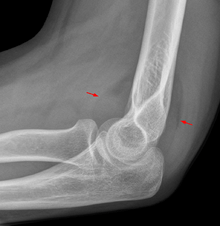

Fat pad sign

On an elbow X-ray, the fat pad sign, also known as the sail sign, suggests an occult fracture. Its name derives from the fact that it has the shape of a spinnaker (sail).[1] It is caused by displacement of the fat pad around the elbow joint. Both anterior and posterior fat pad signs exist, and both can be found on the same X-ray.

In children, a posterior fat pad sign suggests a condylar fracture of the humerus. In adults it suggests a radial head fracture. The fat pad sign only occurs after an intra-articular fracture.

The fat pad sign is invaluable in assessing for the presence of an intra-articular fracture of the elbow. An anterior fat pad is often normal. However a posterior fat pad seen on a lateral x-ray of the elbow is always abnormal. The patient will be unable to flex their elbow and requires orthopaedic input.[2]

The posterior fat pad is normally pressed in the olecranon fossa by the triceps tendon, and hence invisible on lateral radiograph of the elbow.[3] When there is a fracture of the distal humerus, or other pathology involving the elbow joint, inflammation develops around the synovial membrane forcing the fat pad out of its normal physiologic resting place. This is visible as the "posterior fat pad sign" and is often the only visible marker of a fracture, particularly in the pediatrics population.